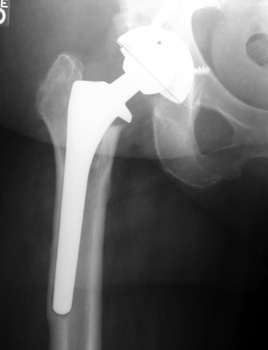

ACETABULAR COMPONENT

Migrating acetabular cup

Very abnormal positioned cup. No comparison radiographs were available. Current radiographs demonstrates markedly tilted cup which has migrated laterally from pelvis.